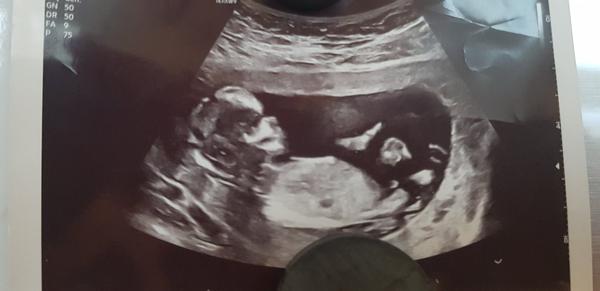

@adelaide131 to víte že může aspoň tedy muj případ tohle jsem viděla v 15tt a od té doby údajně opět holka ja bych si zase z celého srdce přála konečně syna ale neni nam dáno 😪